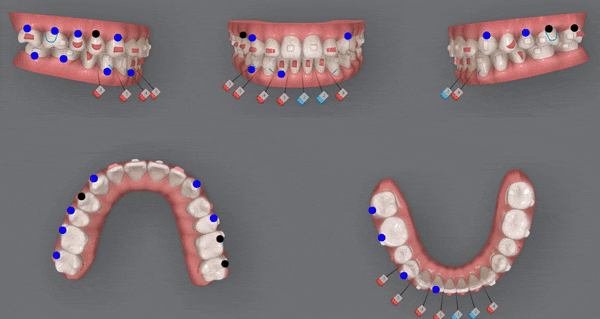

2nd(31개)

두번째 클린체크에서도

우측 아래 치아 전체를

뒤로 미는것에 중점을 두어

큰 어금니들을 먼저 뒤로 밀며 생기는 사이의 틈을 이용해

앞니들을 가지런하게 배열해주었습니다.

어금니들의 대 이동!

쉽지 않은 과정이었지만 닥터킴은 섬세한 치료의 마무리를 위해

다음 클린체크를 이어나가셨습니다 :)

3rd(29개)

위 사진은 세번째 클린체크를 모두 마친후의 사진입니다

어금니들이 제 위치를 찾고 정중선이 맞춰졌습니다